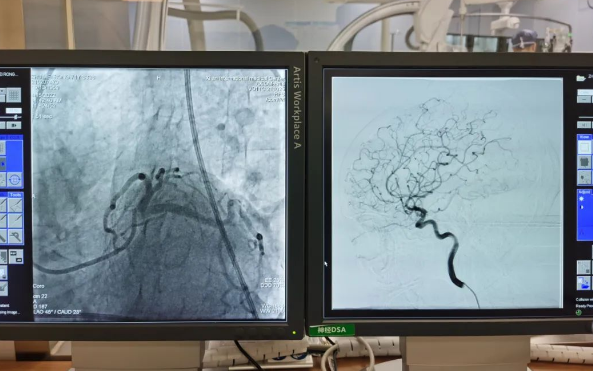

術(shù)前準(zhǔn)備就緒后,心內(nèi)二病區(qū)曾廣偉主任、高釗副主任醫(yī)師、神外科陸丹副主任醫(yī)師共同為患者行腦血管造影術(shù) 冠狀造影術(shù)。術(shù)后,朱奶奶恢復(fù)良好。

陸丹副主任醫(yī)師介紹,由于腦血管疾病和心血管疾病有著共同的病理變化基礎(chǔ)——動脈粥樣硬化,臨床中,兩類疾病交叉存在的情況十分多見?!靶哪X同治”的模式不僅能讓患者獲得較好治療,還能夠降低患者就醫(yī)的時間成本和經(jīng)濟(jì)成本。